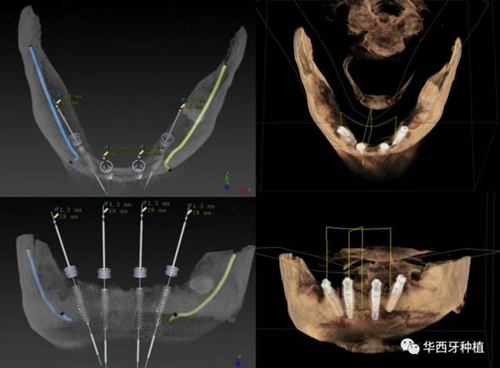

對于傳統(tǒng)的all-on-four術(shù)式,吳教授加入了微創(chuàng)的指導(dǎo)思想,設(shè)計時同樣加入數(shù)字化三維重建與修復(fù)一體化設(shè)計,增加了手術(shù)的可控性,同時極大減輕了患者的創(chuàng)傷程度,縮短了修復(fù)周期。

演講結(jié)束前,吳教授再次提到了數(shù)字化對口腔全口牙缺失種植修復(fù)一體化的重要性,構(gòu)建一體化的數(shù)字化種植修復(fù)流程,不僅能輔助手術(shù),更是簡化修復(fù)和確保遠期療效的一把利器。